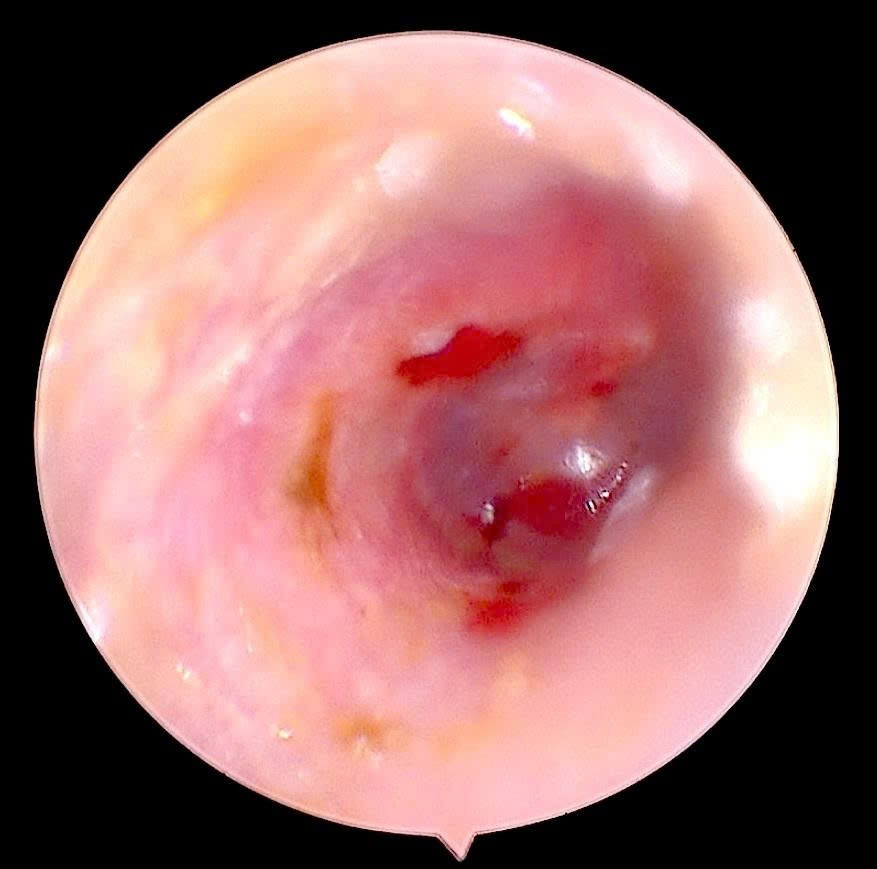

Qua thăm khám và nội soi tai, bác sĩ phát hiện một dị vật là côn trùng còn nguyên vẹn, kích thước khoảng 0,5 cm, nằm sâu trong ống tai phải. Côn trùng di chuyển trong tai khiến màng nhĩ tổn thương, sưng nề và xung huyết, gây cảm giác đau nhói và ù tai liên tục.

Côn trùng chui trong ống tai gây tổn thương - Ảnh BVCC